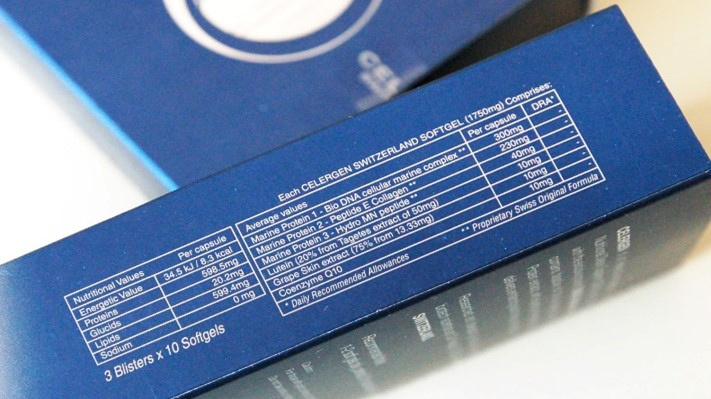

What is it made of?

The potent active key ingredient is a proprietary Cellular Marine Complex that is extracted from the DNA of deep-sea marine life, which through nearly 30 years of research has been associated with powerful anti-aging properties.

Other ingredients include Peptide E Collagen, which reinforces skin elasticity, Hydro MN Peptide, which plays a critical role in the rejuvenation of cartilage, and Natural Lutein, Coenzyme Q10 and Selenium. This synergistic blend restores the firm, youthful complexion you desire.

Each box of Celergen contains 30 soft gels for 1-month consumption.

Recommend intake: 1-2 soft gels daily, preferably 20 minutes before breakfast. Treatment regime 3-6 months.